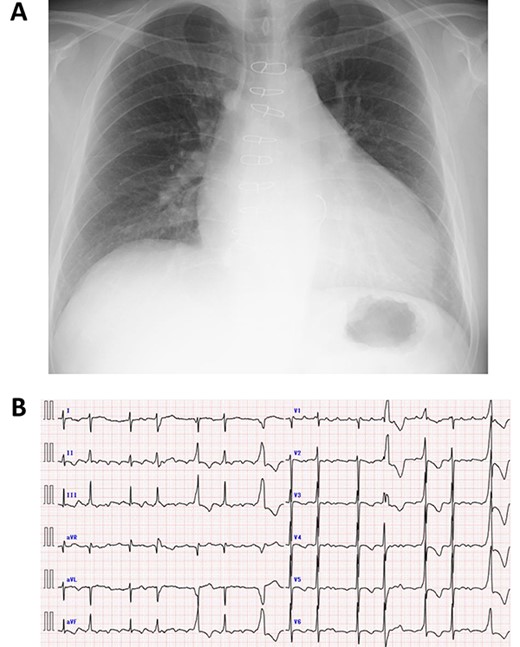

Immediately after the operation, echocardiography revealed improved cardiac function: left ventricular ejection fraction of 37% (Fig. 3A and B). Postoperative course was uneventful and the patient was discharged 2 weeks post operation. Fourth year follow-up revealed further improvement in cardiac function; left ventricular ejection fraction of 42%. The patient continues to do well with NYHA class I status.

Postoperative echocardiography of left ventricle in systolic (A) and diastolic (B) phases.